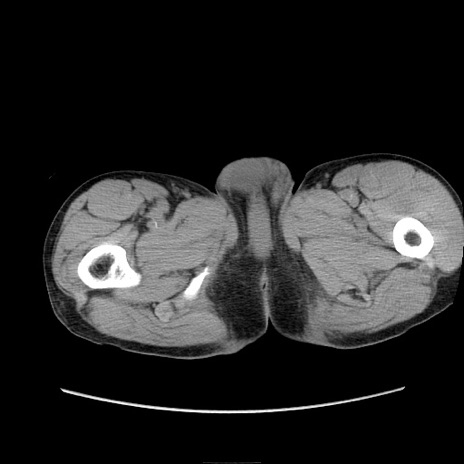

症例11(横断像)

【症例】 60歳代男性

【主訴】 下腹部痛

【現病歴】 本日夜中より下腹部痛の症状認め、受診。

【既往歴】 膀胱癌(膀胱全摘+尿管皮膚瘻術) 、胃癌術後

【身体所見】 BT 35.3℃、PR 58/min、BP 136/98mHg、腹部平坦、軟、腸蠕動音±、ストマ留置あり、左上腹部~正中部に圧痛あり、反跳痛なし。

【データ】WBC 5100、CRP0.01